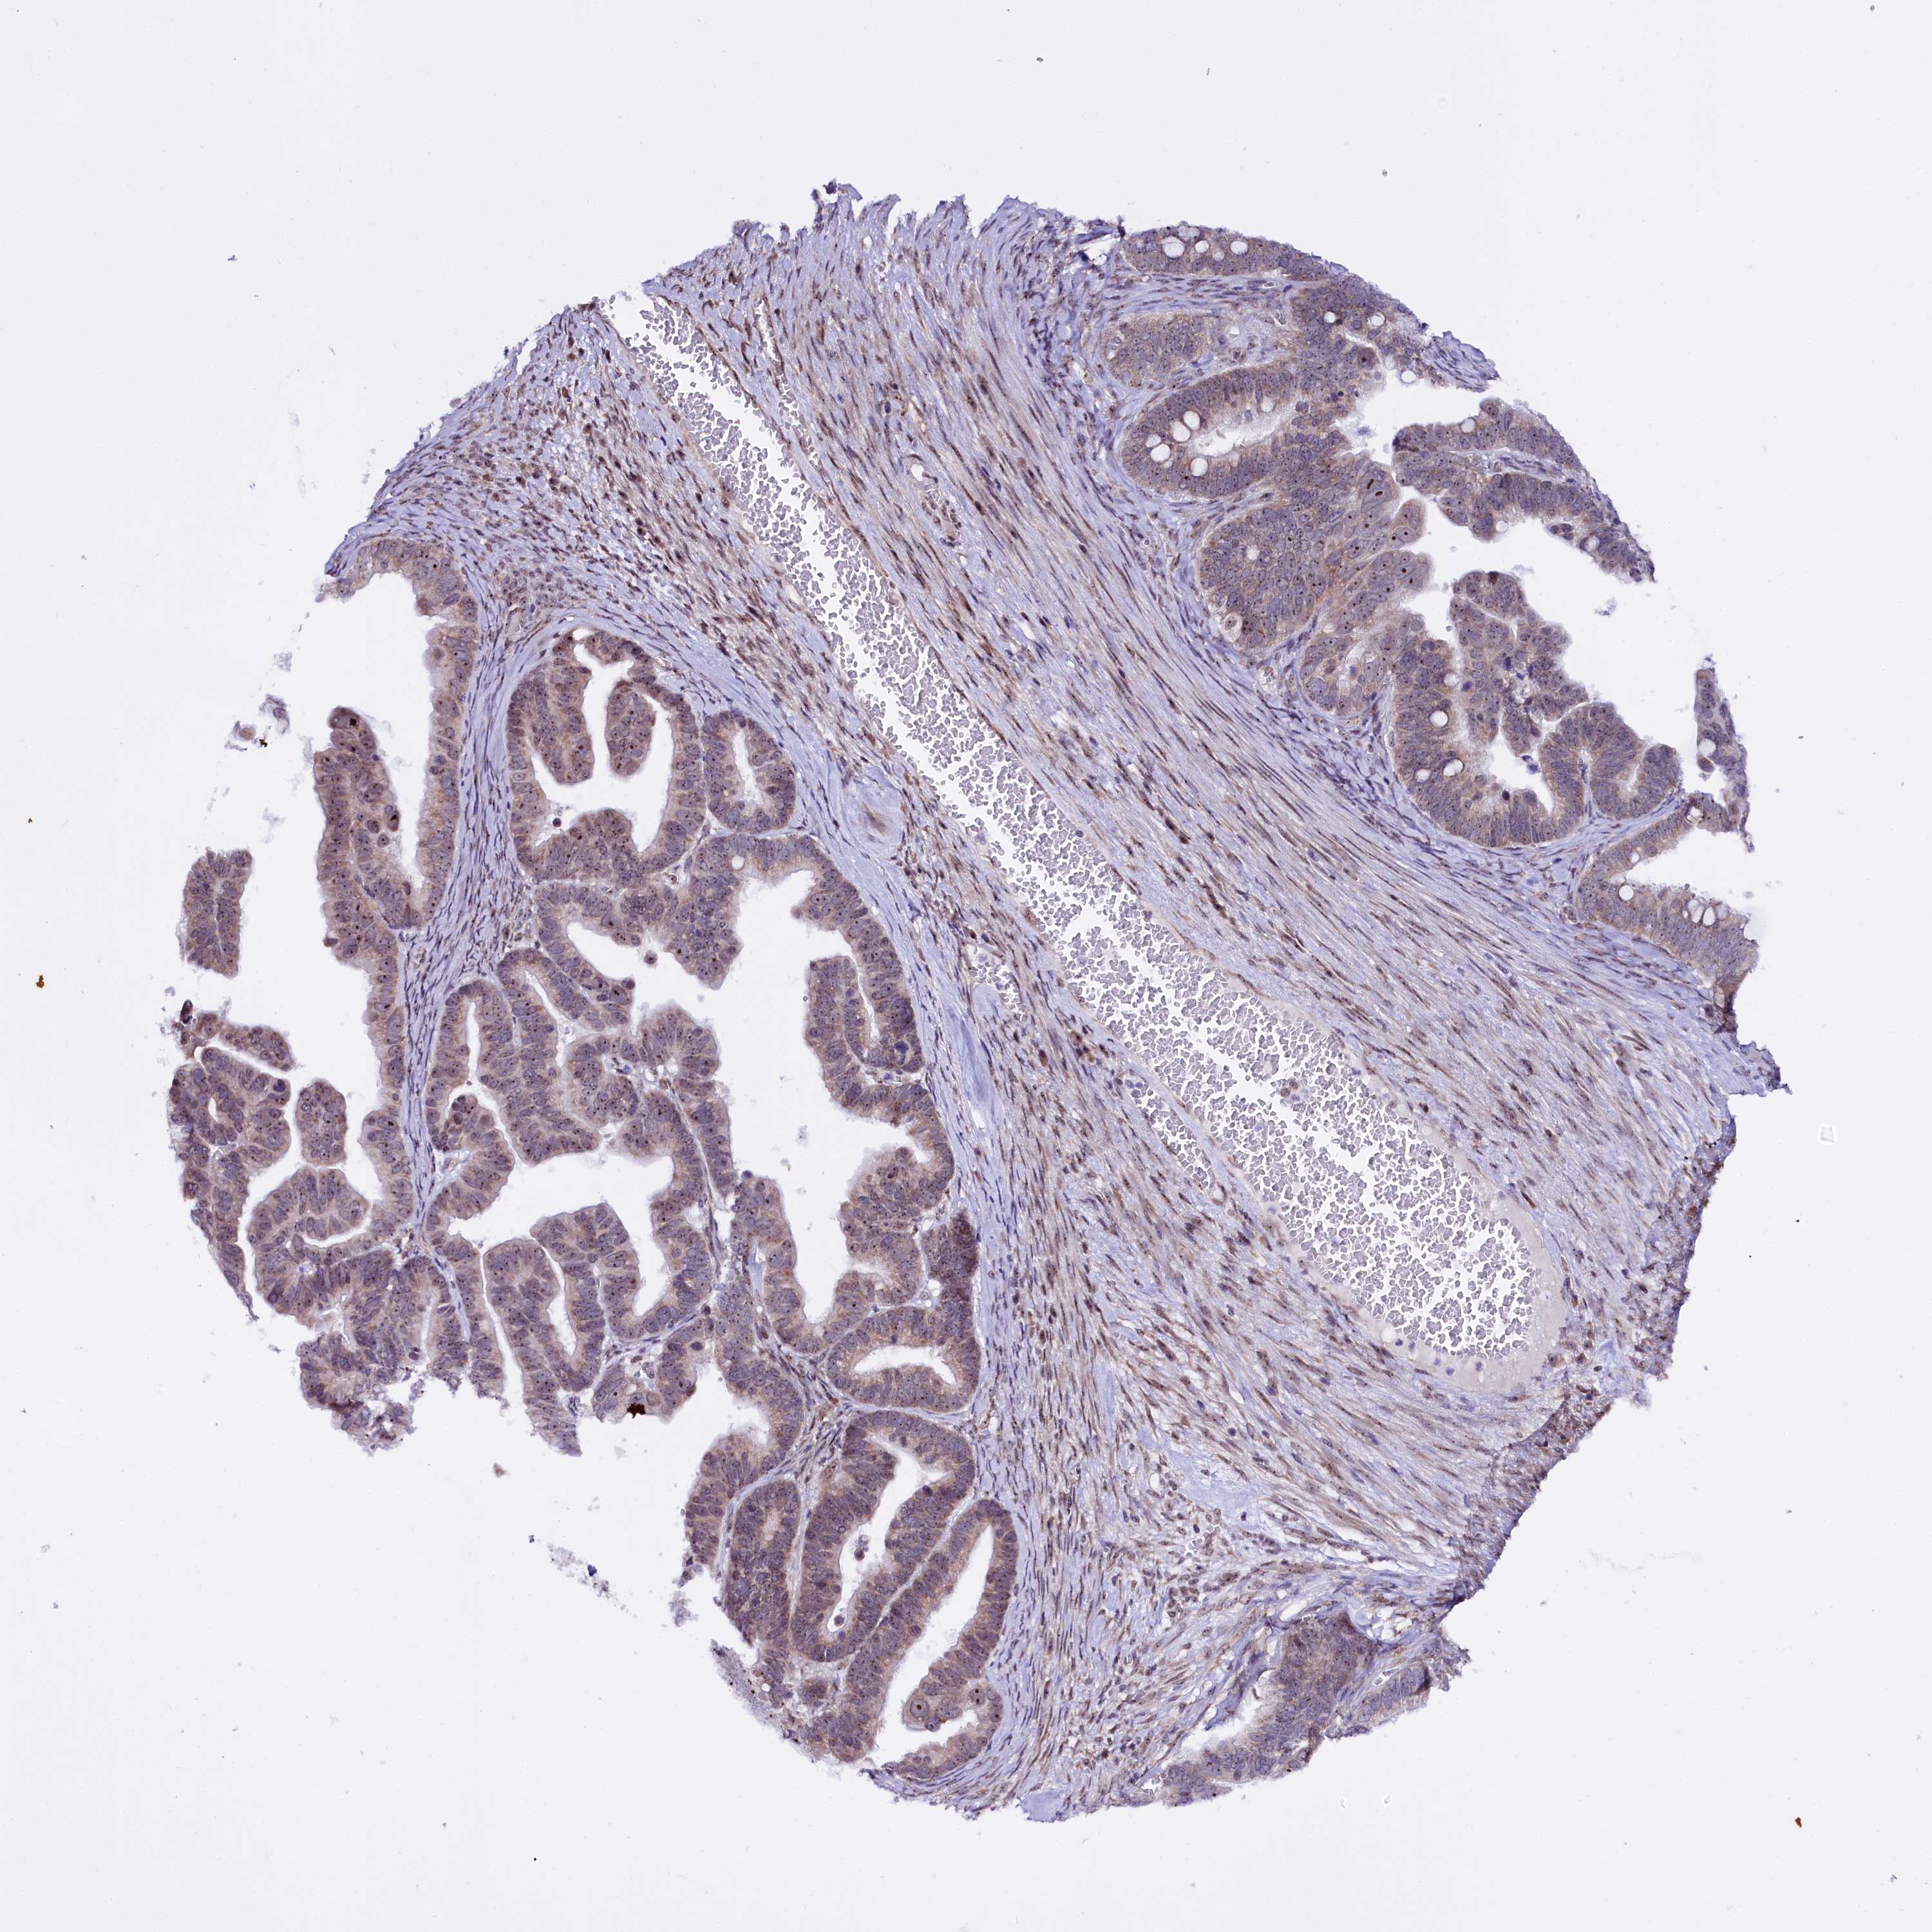

OVARIAN CANCER - Protein expressioni

A mouse-over function shows sample information and annotation data. Click on an image to view it in a full screen mode. Samples can be filtered based on level of antibody staining by selecting one or several of the following categories: high, medium, low and not detected. The assay and annotation is described here.

Note that samples used for immunohistochemistry by the Human Protein Atlas do not correspond to samples in the TCGA dataset.

Antibody stainingi

Antibody staining in the annotated cell types in the current human tissue is reported as not detected, low, medium, or high, based on conventional immunohistochemistry profiling in selected tissues. This score is based on the combination of the staining intensity and fraction of stained cells.

Each image is clickable and will lead to virtual microscopy that enables deeper exploration of all samples and also displays staining intensity scores, fraction scores and subcellular localization as well as patient and tissue information for each sample.

Antibody HPA038860

Staining

High

Medium

Low

Not detected

Intensity

Strong

Moderate

Weak

Negative

Quantity

>75%

75%-25%

<25%

None

Location

Nuclear

Cytoplasmic/membranous

Cytoplasmic/membranous,nuclear

Cystadenocarcinoma, serous, NOS

Carcinoma, endometroid

Cystadenocarcinoma, mucinous, NOS

Carcinoma, NOS